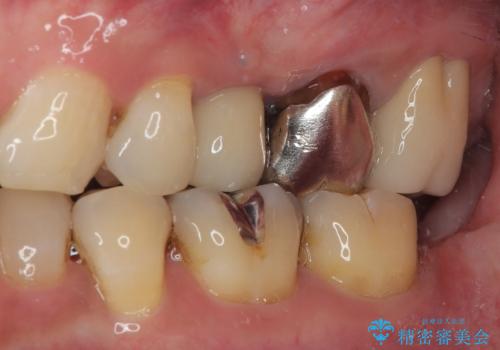

- 銀歯がとれたのでやり替えたいとのことで来院された患者様です。何度も同じ部位の銀歯の脱離を繰り返しており、メタルインレーの不適合も認めていたためオールセラミッククラウンにて補綴治療を行っていくことにしました。

拡大鏡視野下で、セラミックの被せもの、虫歯の除去を行い、オールセラミッククラウンに適した形に整えました。